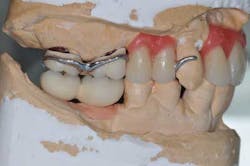

Figs. 6 a, b, c, and d: RPD framework try-in, bite record with mandibular implant-supported metal frameworks and mounting